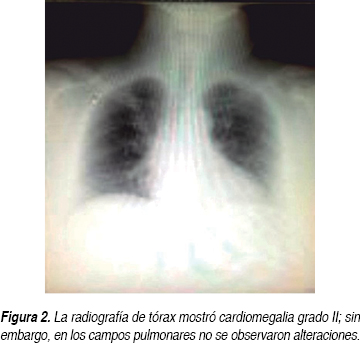

Una paciente del sexo femenino de 51 años de edad ingresó al servicio de urgencias de nuestro hospital el día 16 de octubre del 2013. Entre sus antecedentes de importancia se destacó la presencia de obesidad mórbida con un índice de masa corporal (IMC) de 47.6, negando toxicomanías. Ella refirió que 12 años atrás había sido atendida en el Hospital Universitario de la Ciudad de Monterrey, Nuevo León, México, debido a un tromboembolismo pulmonar (TEP) agudo, colocándosele filtros permanentes colocados en la vena cava inferior (FCVI). Se le diagnosticó, además, deficiencia de proteína C y S, la cual fue confirmada recientemente cuatro meses antes de su actual ingreso hospitalario, en el Hospital No. 25 del Instituto Mexicano del Seguro Social (IMSS), en donde fue atendida por un episodio de tromboflebitis en el brazo derecho. También se le diagnosticó diabetes mellitus tipo 2 (DM2) e hipertensión arterial sistémica (HAS) hace un año. Ella describió que dos semanas antes de su ingreso comenzó a manifestar disnea tras realizar esfuerzos físicos moderados. El día 16 de octubre se agregó a esta sintomatología dolor subesternal intenso de carácter opresivo, además de disnea severa en reposo y diaforesis profusa fría con irradiación a brazo izquierdo. Su exploración física no arrojó datos relevantes a nivel cardiopulmonar, destacándose solamente obesidad exógena, presión arterial de 170/100 mmHg, frecuencia cardiaca de 86 por minuto y una frecuencia respiratoria de 22 por minuto, sin fiebre. La paciente describió además dolor de intensidad moderada, continuo, en la cara posterior de la pierna izquierda con signo de Homman positivo, aunque la revisión no reportó cambios de coloración de tegumentos en esa zona. El electrocardiograma tomado en urgencias (Figura 1) reportó un ritmo sinusal con frecuencia de 90 por minuto, PR de 0.12, QRS de 0.08 segundos y AQRS a - 60 grados, reportando como única alteración un hemibloqueo de fascículo anterior izquierdo. La radiografía de tórax posteroanterior no mostró alteraciones significativas (Figura 2). Bajo el diagnóstico de crisis hipertensiva con sospecha de síndrome coronario agudo (SICA), la paciente fue ingresada al servicio de cardiología de este hospital. Le fueron solicitadas enzimas cardiacas en dos determinaciones con creatinfosfoquinasa (CPK) de 70 U/L, fracción muscular-cerebral (MB) de 22 U/L y deshidrogenasa láctica (DHL) de 215 U/L, como valores más altos. La glucosa se documentó en 155 mg/dL, el nitrógeno de la urea en 15 mg/dL y la creatinina en 0.6 mg/dL. El sodio fue de 139 meq/L y el potasio de 4.2 meq/L. La biometría hemática reportó hemoglobina de 13.3 g/dL, hematocrito de 42.1%, leucocitos de 9,330/mm3 con neutrófilos de 70.1%, linfocitos de 21.5%, eosinófilos de 1.75% y plaquetas de 259,000/mm3. La gasometría venosa mostró un potencial de hidrogeniones (PH) de 7.35, una presión parcial de dióxido de carbono (PCO2) de 42 mmHg y una presión parcial de oxígeno (PO2) de 46 mmHg, así como una concentración de bicarbonato (HCO3) de 23.2 mmol/L y un exceso de base (EB) de - 2.4 mmol/L. El tiempo de protrombina al ingreso fue de 32.7 segundos con testigo de 13 segundos con la relación internacional normalizada (INR) de 2.55. El tiempo de tromboplastina parcial (TTP) de 33.2 segundos con testigo de 30 segundos y el fibrinógeno de 533.0 mg/dL. No le fue solicitado el dímero D. A la paciente se le realizó un ecocardiograma transtorácico, el cual documentó fracción de eyección del ventrículo izquierdo (VI) normal de 63%, dimensiones intracavitarias normales y disfunción diastólica por trastorno de relajación del VI, sin observarse trastornos de la movilidad y/o dilatación del ventrículo derecho. No se documentó insuficiencia tricuspídea, y el tiempo de aceleración del flujo de la arteria pulmonar se registró en 183 milisegundos.